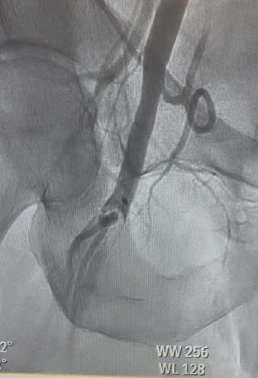

Urgent intervention was undertaken. Left femoral access was obtained, and a 6F sheath was inserted for up-and-over access. A 5F Omni™ Flush catheter (AngioDynamics) was advanced into the right external iliac artery, and angiography revealed thrombus surrounding the previously placed MANTA closure device (Teleflex®). The catheter was exchanged for a 7F, 45-cm Pinnacle sheath (Terumo), and a 7F Lightning Bolt® aspiration catheter (Penumbra) was advanced for clot retrieval. The thrombus “lollipopped” onto the catheter; therefore, the entire aspiration system, including the sheath, was removed. A significant amount of clot was extracted (Figure 2).

Manual pressure was applied to achieve hemostasis at the left femoral access site. Following the procedure, pulses were palpable and +2 bilaterally. The patient tolerated the intervention well and left the catheterization lab in stable condition. This highlighted a very important intervention and the use of the Penumbra coronary CAT RX and peripheral Lightning Bolt System for multiple successful interventions.